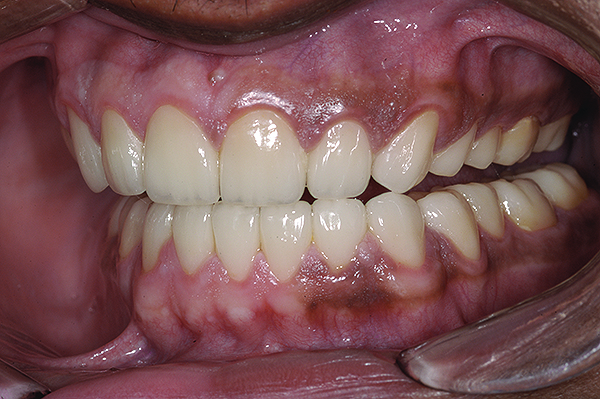

Figure 20. Postoperative 1:2 retracted frontal view.

Figure 20